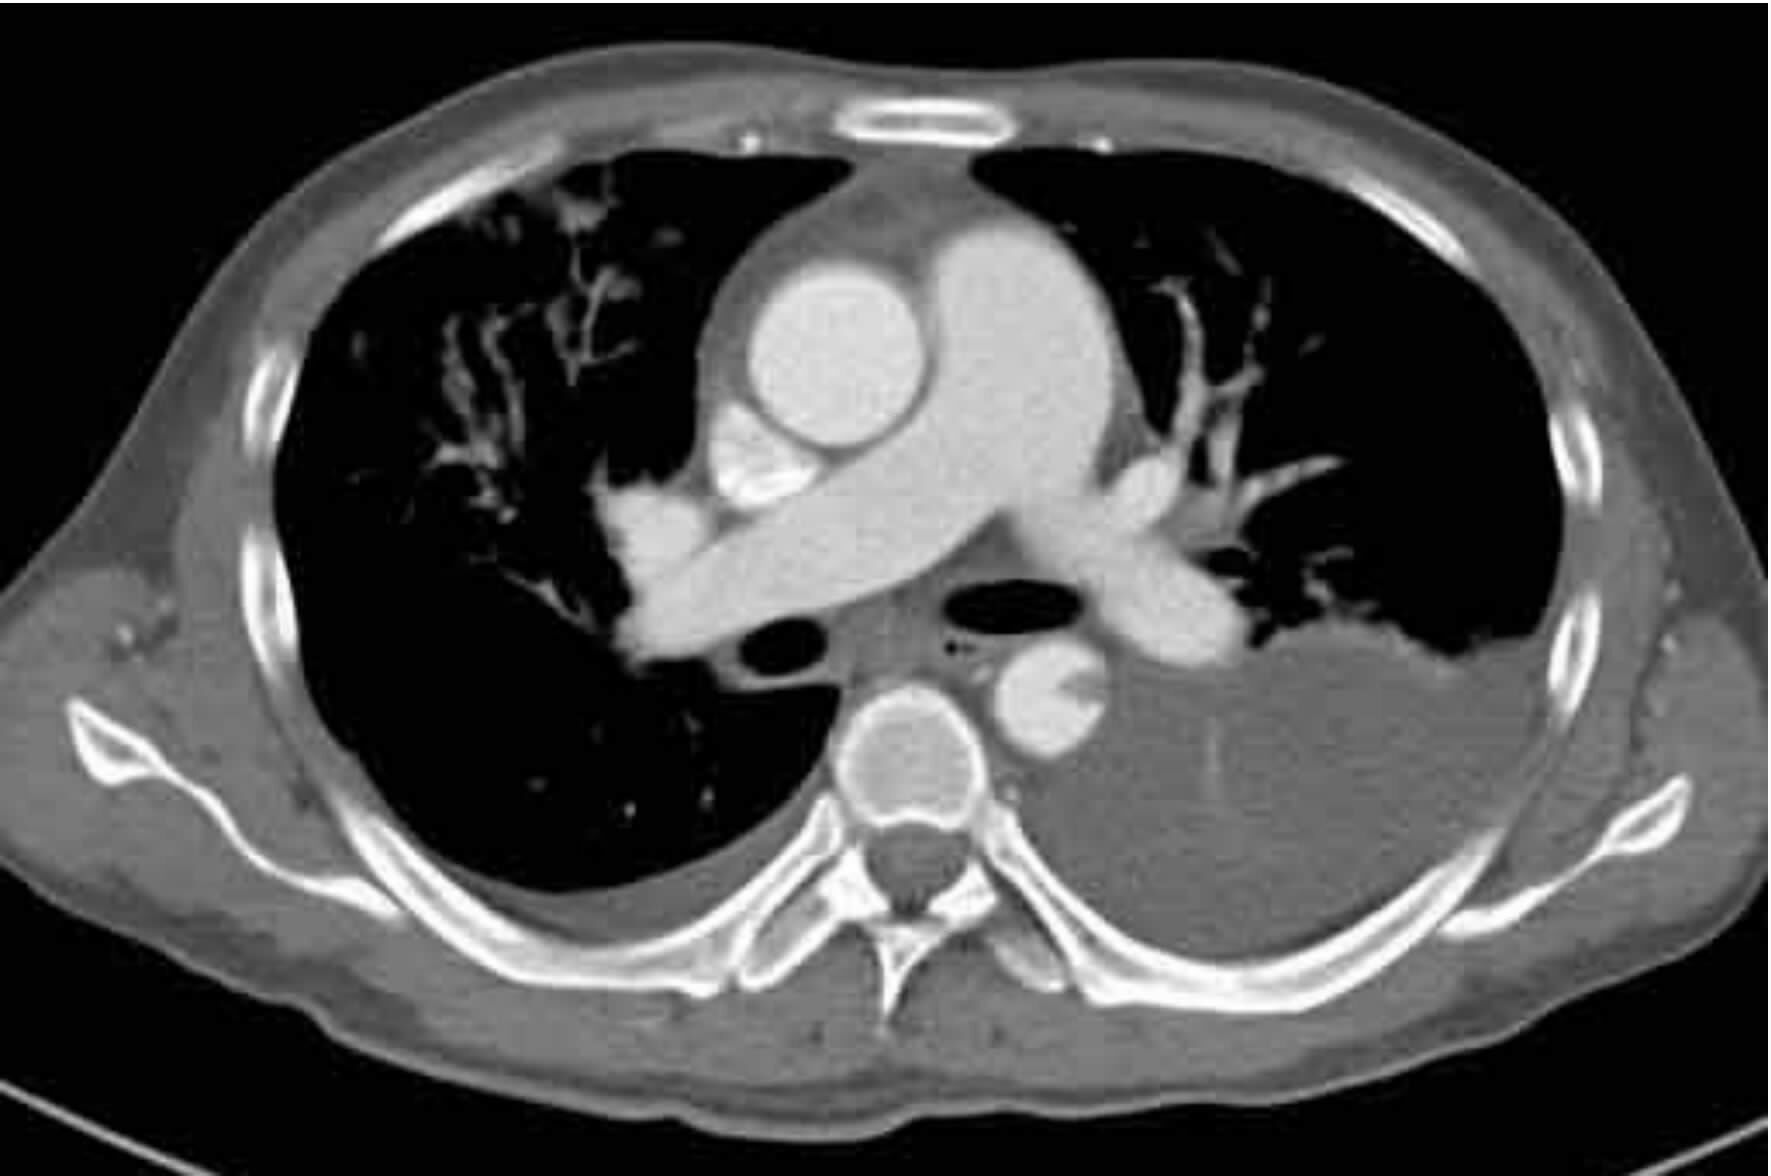

2 结果37例钝性胸主动脉损伤,CTA征象表现为内膜瓣、轮廓异常、血栓、动脉收缩、假性动脉瘤、主动脉夹层6种情况。①内膜瓣:内膜瓣为增强的主动脉管腔内可见一个或多个弧形弱化区(图 1)。②主动脉轮廓异常:表现为主动脉管壁或轮廓不规则,圆形的主动脉横切面发生变化,(图 2)。③假性动脉瘤:指主动脉壁破裂出血,形成主动脉壁外的血肿,主动脉管腔与不规则瘤腔结合处呈锐性边缘(单侧或双侧),(图 3)。④主动脉夹层:内膜片和主动脉真假两腔形成是诊断夹层动脉瘤的基本征象。内膜片将血管分为真假两个腔隙。增强早期真腔密度高于假腔,随时间延迟,假腔密度逐渐增高,假腔密度可等于或高于真腔,(图 4)。⑤动脉收缩表现为损伤节段主动动脉直径小于正常节段动脉直径(图 5)。⑥血栓;主动脉腔内息肉样低密度区(图 6)。本组37例钝性胸钝性胸主动脉损伤患者,CTA征象存在内膜瓣34例(91.8%),主动脉轮廓改变或腔异常37例(100%),动脉收缩17例(45.9%),主动脉夹层10例(27.0%),假性动脉瘤21例(56.7%),血栓1例(2.7%)。

| 图 3 主动脉峡部损伤假性动脉瘤征象,左锁骨下动脉分支受压 Figure 3 Pseudoaneurysm sign of aortic isthmus injury and compression of the left subclavian artery. |